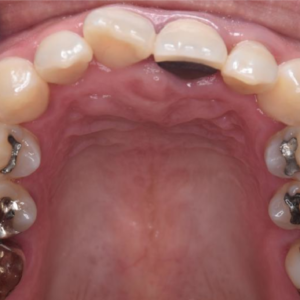

左上3番目の歯がなかなか生えてこないということを主訴に来院された子供さん(13歳)です。 レントゲン写真にて歯の位置を確認しました所、2番目の歯の下に位置しており、かなり方向がずれていることが判明しました。 そこで埋伏歯 […]